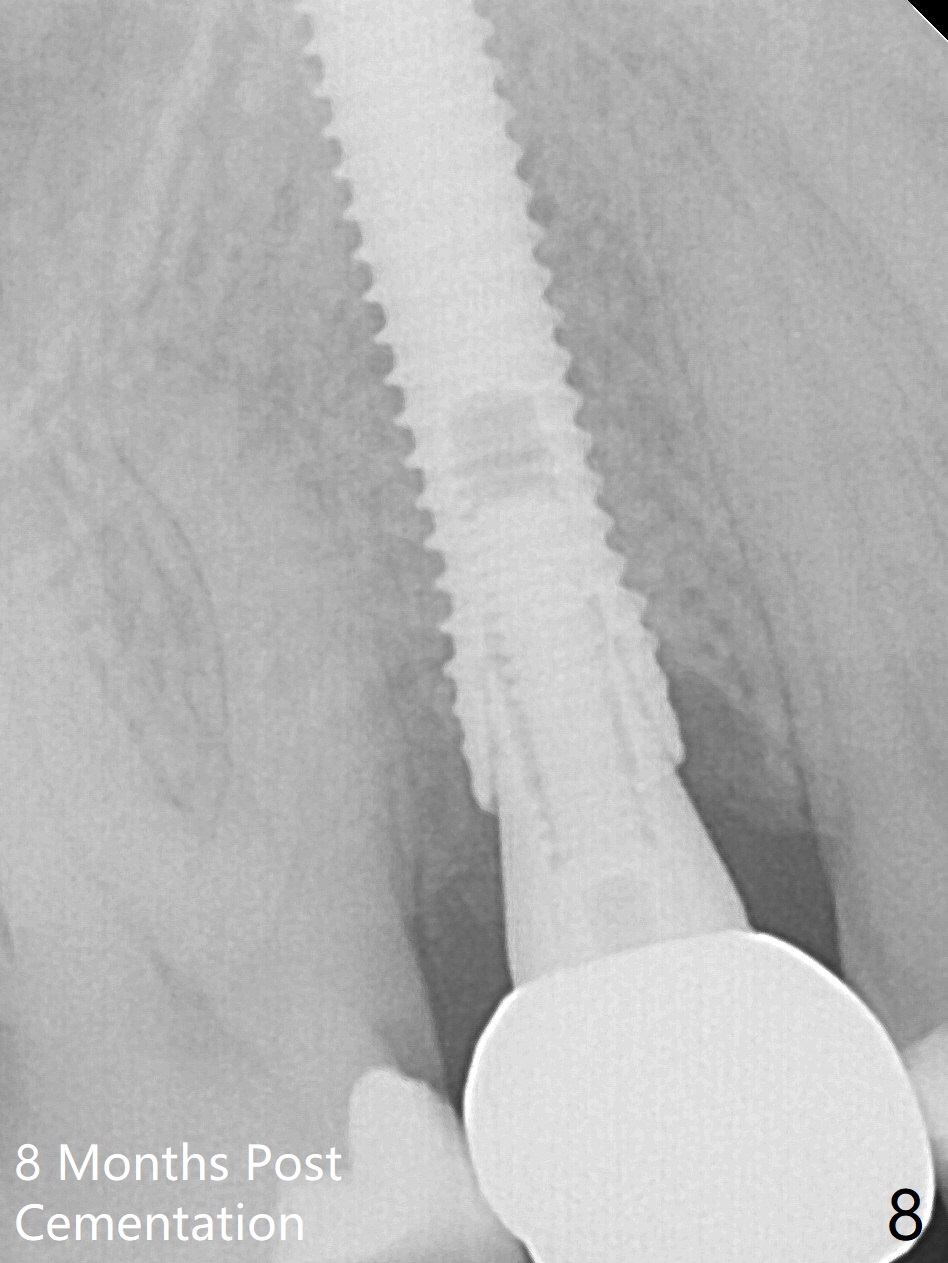

When the tooth #4 with vertical root fracture (Fig.1) is extracted, the buccal plate is found to be lost. The lowest point of the defect is shown as black dashed line in Fig.2 (yellow dashed line: sinus floor). After use of 2.5 mm reamer for 21 mm (buccal gingival level) and 3.0 mm reamer for ~17 mm, a 3.8x15 mm dummy implant is placed with 30 Ncm and 1.85 mm apical space (Fig.3 pink outline). A 3.8x18 mm (definitive) implant is placed with <40 Ncm with the implant plateau apical to the lingual crest (Fig.4,5). The buccal plate defect is repaired by Vanilla Graft (Fig.6 *) before and after insertion of a 4.5x4(3) mm abutment. The buccal plate defect seems to being repaired 4 months postop (Fig.7). Occlusal wear suggests bruxism, which is also associated with the root fracture. Night guard is recommended. The defect repair is close to completion 8 months post cementation (Fig.8). The crown/abutment is found to be loose 1 year 4 months post cementation and retightened without checking whether there is clinical 2nd DO caries of #3 (Fig.9, "sensitive to water pik"). A few days later, DO composite is being removed. It is difficult to determine whether the 2nd DO caries or gap has been removed with the neighboring crown in place. When the crown/abutment is removed and gingival retractions are inserted, there is no decay. The gap is removed. With Toflemire in place, the crown/abutment is reseated and hand tightened; after packable composite, the crown/abutment is removed, there is no more DO gap.